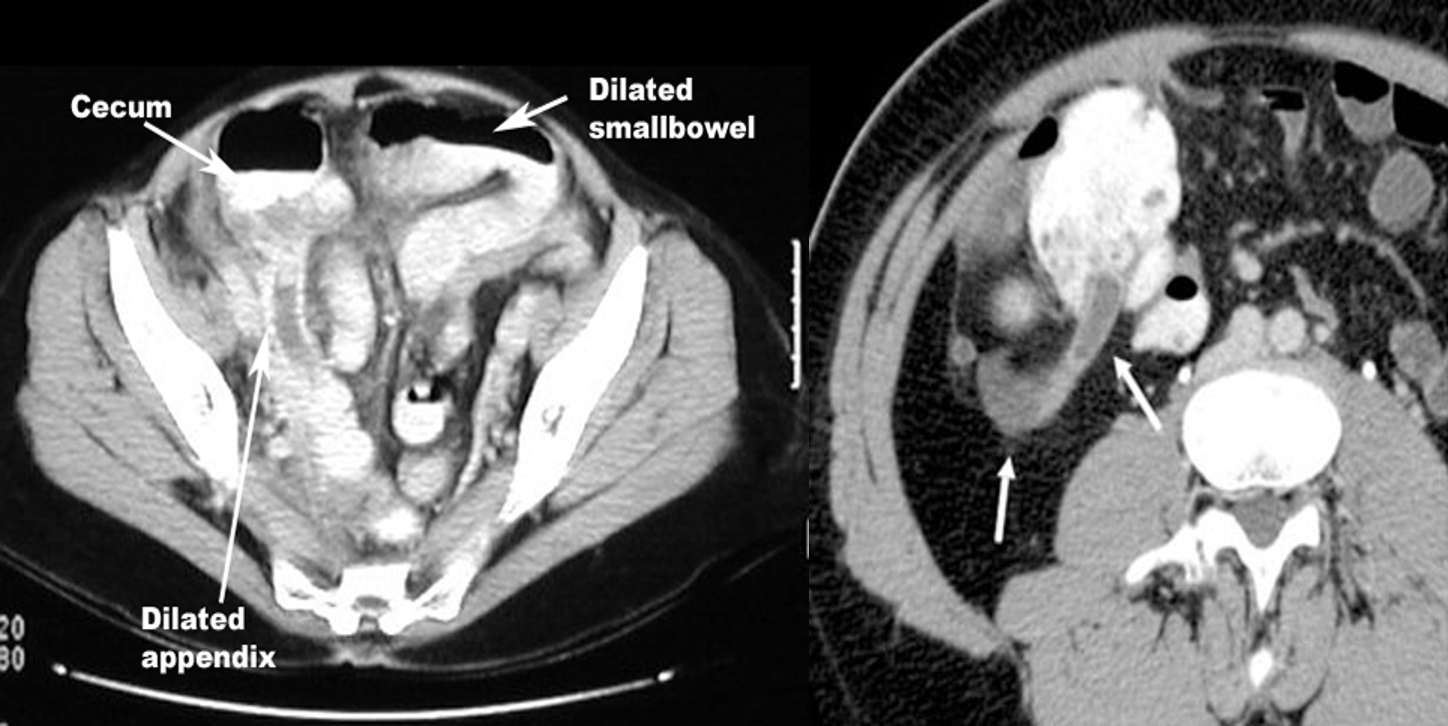

- CT image of acute appendicitis